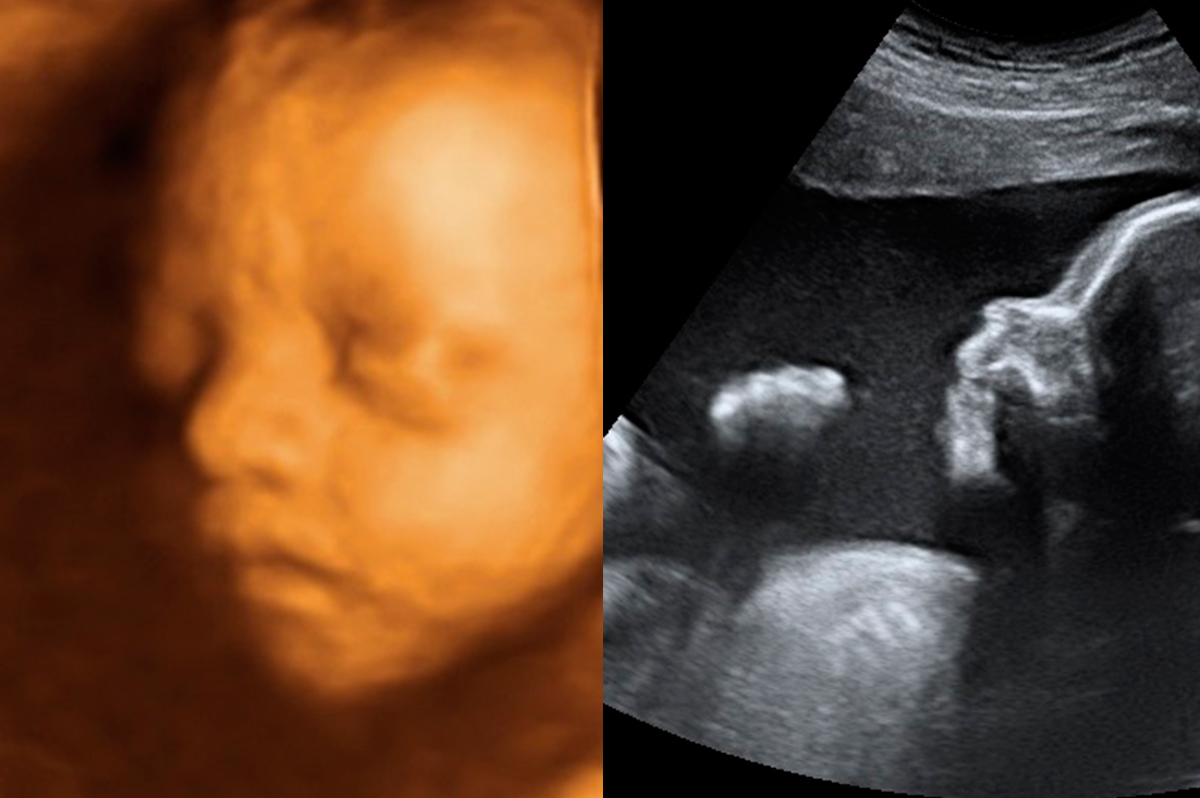

Primer nacimiento en la provincia de Sevilla tras ablación por radiofrecuencia en sanidad pública.

Ablación de miomas por radiofrecuencia: un tratamiento ambulatorio definitivo.

Descripción de técnica mínimamente invasiva para el tratamiento de los miomas: la ablación por radiofrecuencia.